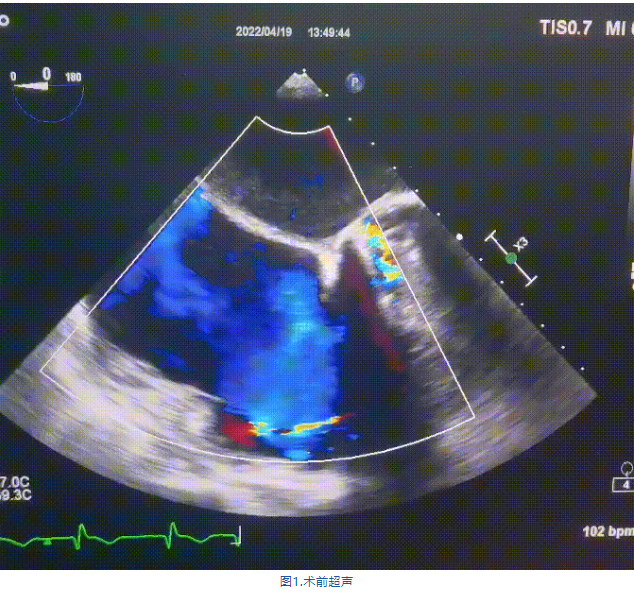

術(shù)前超聲提示:

1.右心、左房明顯增大;

2.二尖瓣人工機(jī)械瓣功能正常,無(wú)瓣周漏;

3.三尖瓣環(huán)巨大擴(kuò)張,收縮期瓣葉對(duì)合不攏,收縮期三尖瓣房側(cè)見(jiàn)大量反流信號(hào),反流面積15-20cm²,TRVmax:240cm/s,跨瓣壓差:23 mmHg。